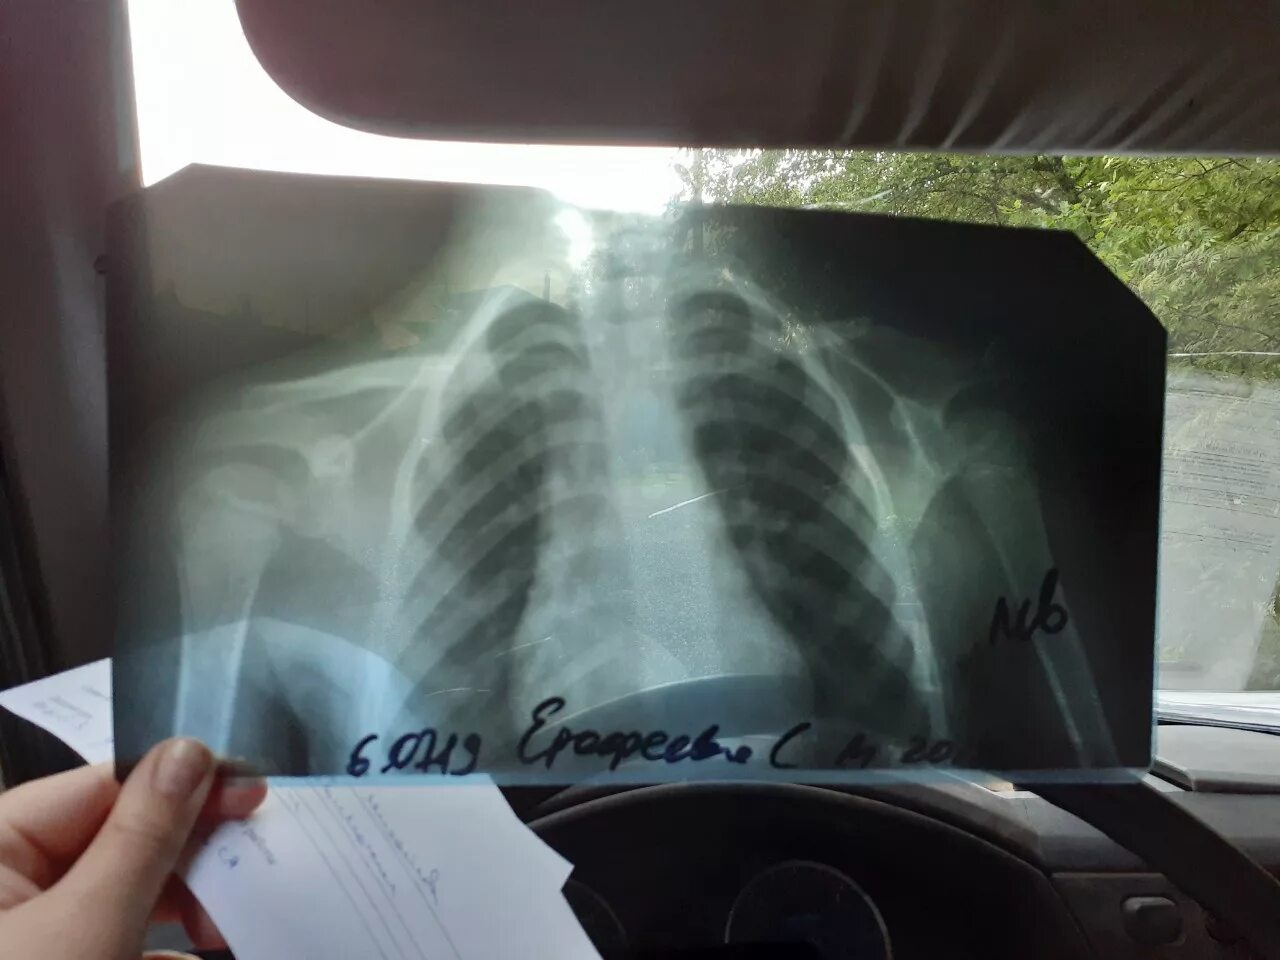

Сколько срастается ребро при переломе